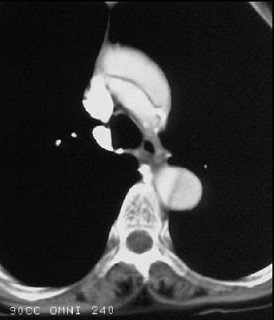

男,64岁,突感胸部剧痛2h,呈撕裂样,并向背部放射,有高血压病史10年,含服硝酸甘油3片不能缓解,CT检查如图所示。首先应考虑的诊断是 ( ) XN-09481.jpg XN-09482.jpg XN-09483.jpg

• A.主动脉夹层